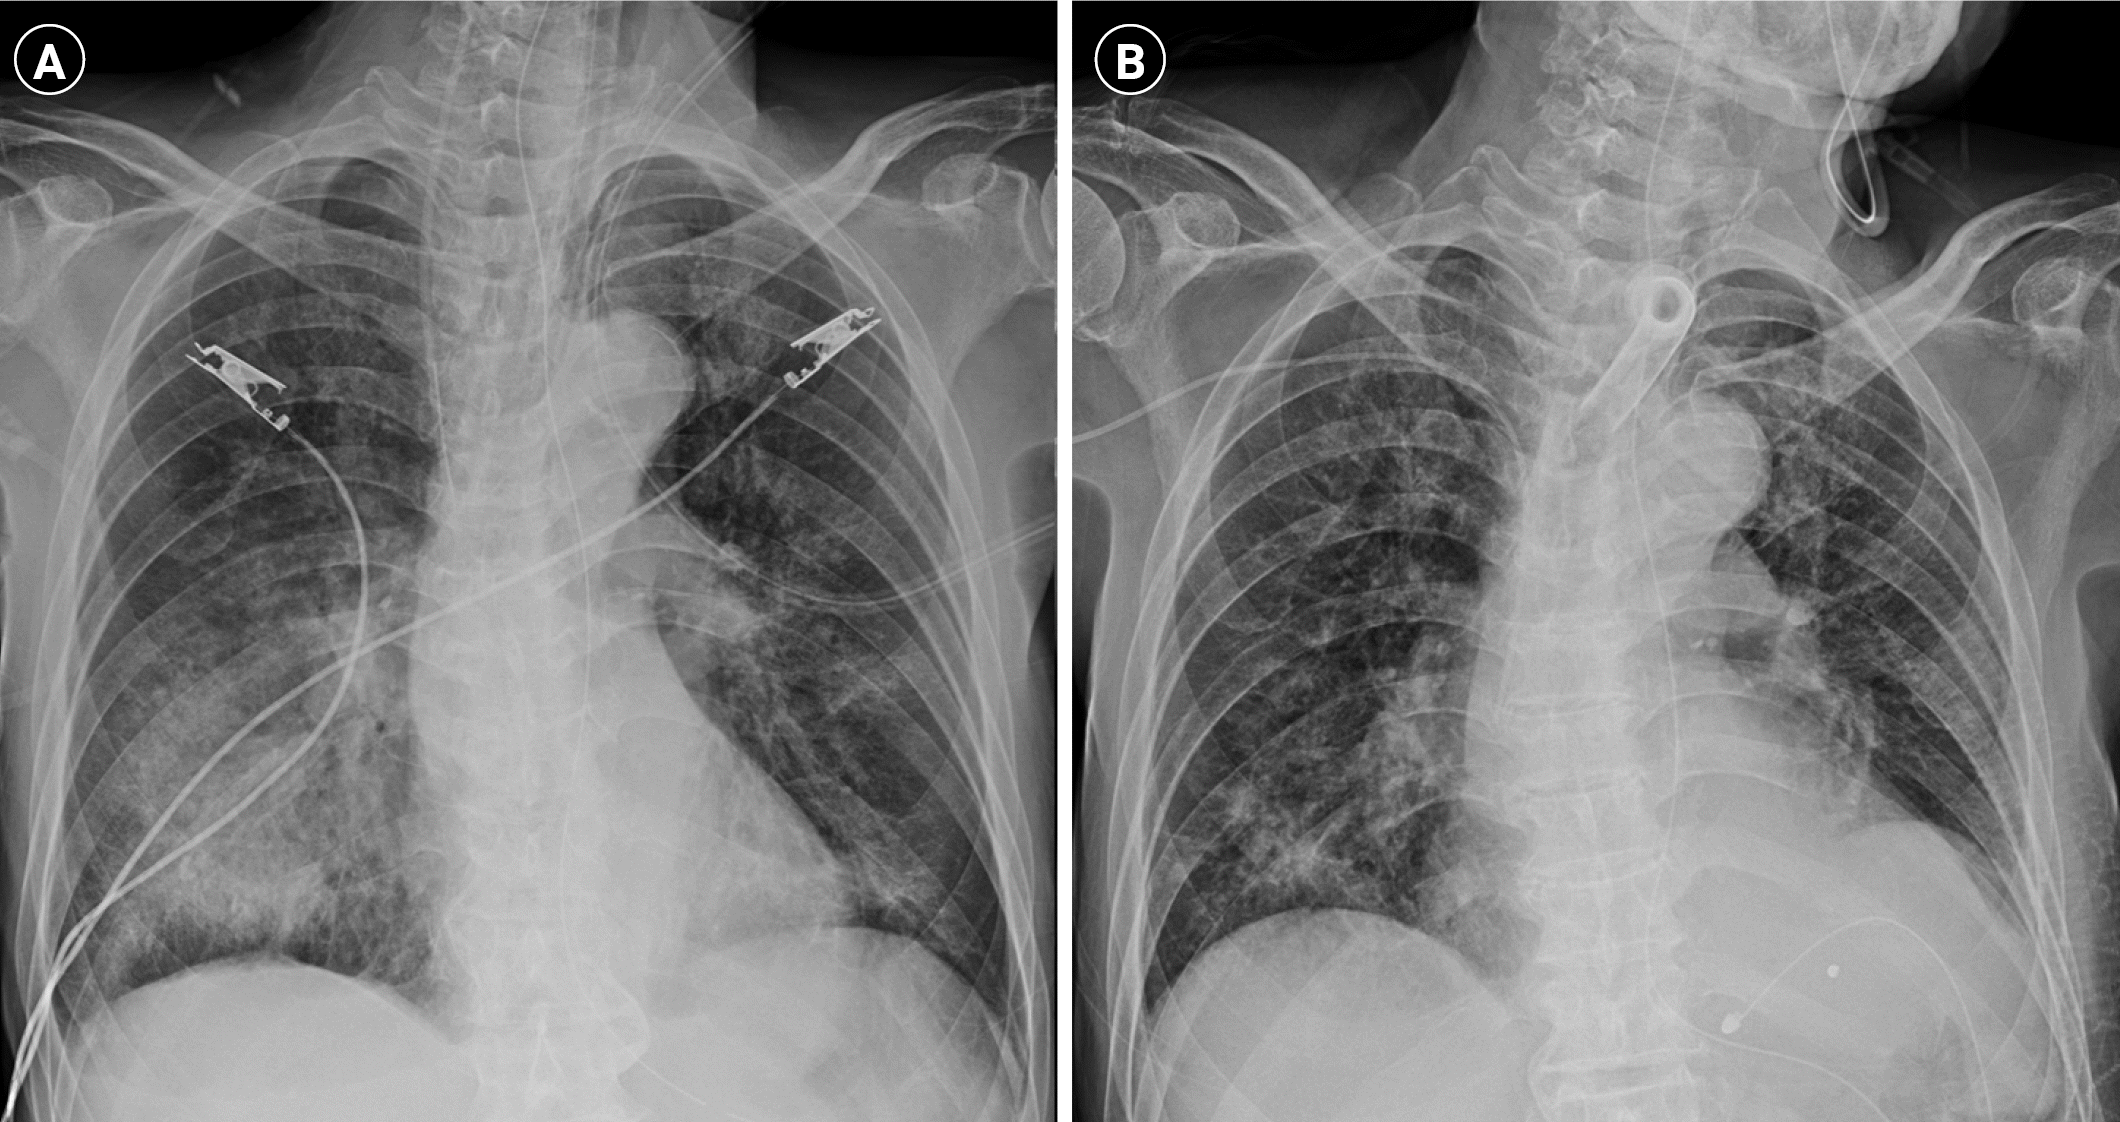

An 85-year-old man with a history of carotid artery stenosis, hyperlipidemia, chronic kidney disease, and dementia was admitted to the intensive care unit (ICU) because of sputum produced 1 day prior and worsening dyspnea on the visit day. Upon admission, the patient was drowsy, with blood pressure 69/37 mm Hg, heart rate 75 beats/min, respiratory rate 22 beats/min, body temperature 36.9 °C, and pulse oxygen saturation 60% at room air. Coarse breath sounds with crackles were heard in both lung fields. Concurrent with mechanical ventilation, adequate intravenous fluid and norepinephrine were administered. The initial serum lactate level was elevated to 2.5 mmol/L. Chest radiograph showed increased opacities mainly in the right lower lung field (Figure 1A). Chest computed tomography revealed multifocal nodules with surrounding ground-glass opacities (GGOs), the “halo sign” in underlying emphysematous lungs, and extensive consolidation with GGO in both lower lobes (Figure 2A and B). The initial white blood cell and absolute neutrophil counts were 3,110/μl and 2,430/μl,, which increased to 8,430/μl and 6,830/μl on the second day, respectively. Non-specific erythematous bronchial mucosa with a large amount of thick, purulent sputum was observed on bronchoscopy, and bronchial lavage and culture were performed. Serum high-sensitivity C-reactive protein (hs-CRP) and procalcitonin levels were 16.47 mg/dl and 20.9 ng/ml, respectively. The broad-spectrum antibacterial agent cefepime was infused immediately. During the first 5 days, the blood platelet count decreased markedly from 103,000 to 65,000 /µl; serum creatinine level increased from 1.7 to 2.0 mg/dl; and serum hs-CRP and procalcitonin levels increased to 18.07 mg/dl and 55.0 ng/ml, respectively. The initial bronchoscopic culture and respiratory virus multiplex tests showed negative results, except the galactomannan (GM) antigen level from bronchoscopic washing was elevated at 1.5. The serum GM antigen level was also elevated at 4.99 (Figure 3). Blood beta-D-glucan (BDG) level peaked at greater than 1,000.0 pg/ml. With suspicion of invasive aspergillosis, oral voriconazole was added on the third day of admission. The patient was not at high risk for multidrug-resistant organism infection related to recent exposure to antimicrobial drugs or hospital admission and was not at high risk for opportunistic infection due to immunosuppression. Ten days later, given that the hs-CRP level was still high at 16.06 mg/dl and the follow-up chest CT images revealed aggravation of nodular consolidations, oral voriconazole was replaced with intravenous liposomal Amphotericin B (Figure 2C). The hs-CRP level finally improved to 3.80 mg/dl 1 week after start of intravenous liposomal Amphotericin B. Finally, Aspergillus fumigatus was cultured on the 33rd day from the endotracheal aspirate sample collected on the 26th day of intensive care. The patient was weaned from the mechanical ventilator on the 40th day of ICU admission in the tracheostomy state and discharged from the ICU after 45 days of intensive care. The follow-up radiograph and CT images showed partial improvement of nodular consolidations (Figure 1B and 2D).

At first, our patient seemed to have no relevant risk factor for invasive aspergillosis, except slight emphysematous change in both lungs on chest CT. However, his serum and bronchial washing GM were positive, and the serum level of BDG [5], another fungal marker, was increased. Further, the radiologic findings were consistent with invasive aspergillosis, e.g., the “halo sign,” contrary to most non-neutropenic patients showing non-specific results [2]. Finally, we diagnosed the patient with probable invasive aspergillosis and prescribed antifungal treatment.

Figure 2.

(A) The coronal view of initial chest computed tomography (CT) shows bilateral multifocal nodules with surrounding ground-glass opacities (GGOs), the “Halo sign” (black arrows), and centrilobular emphysema (white arrowheads) in both lungs. (B) Axial images of the same CT scan reveal multiple nodules with surrounding GGO (black arrows in the above row) in both upper lobes and extensive consolidation with GGO (black arrows in the bottom row) in both lower lobes. (C) The follow-up axial CT images show aggravated nodular consolidations in the upper and lower lobes on the 13th day of admission. (D) The second follow-up axial chest CT images show partial improvement of nodular consolidations in the whole lung fields on the 45th day of admission.